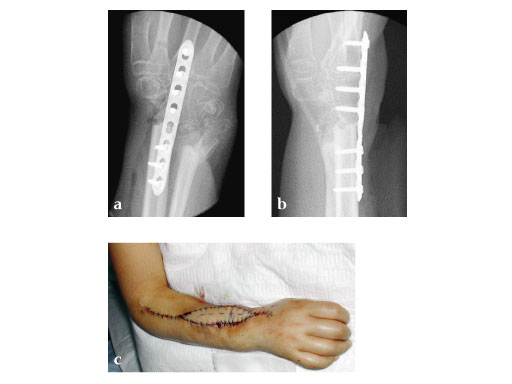

Female, 10 years, after bone tumor (Ewing's sarcoma) resection and allograft implantation, fistula to necrotic allograft.

Fig 1 ab: Preoperative x-rays.

Fig 1 c: Hand without any function.